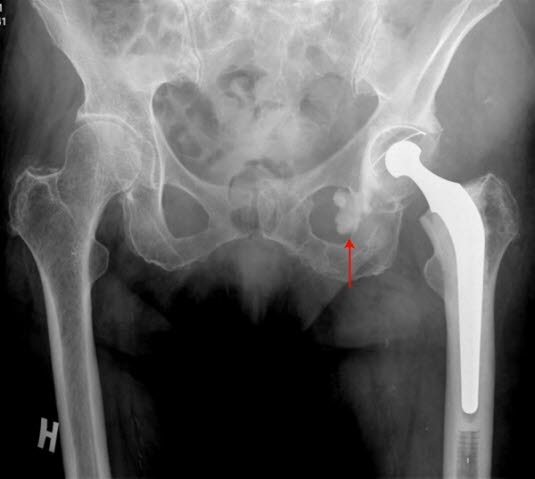

Standardbehandlingen ved invalidiserende artrose hos dem over 50 år er innsetting av hofteprotese, kunstig hofteledd. Det er vanlig å skifte ut både leddhodet (på lårbeinet) og hofteskåla (i hoftebeinet) - det innsettes en såkalt total hofteprotese.

En hofteprotese består som regel av fire komponenter; hode, stamme, kopp og foring. Hodet på en hofteprotese er den delen som forbinder protesens stamme med koppen og utgjør den ene delen av selve proteseleddet. Den andre delen utgjøres av koppen som er festet til bekkenbeinet. Stammen i en hofteprotese er den delen som festes i lårbenet. Når man setter inn en hofteprotese, sager man av lårhalsen for å fjerne lårbenshodet, og man får tilgang til lårbenets marg. Protesestammen settes ned i dette hulrommet, og den kan enten festes til lårbenet ved hjelp av bensement, eller ved såkalt usementert teknikk.